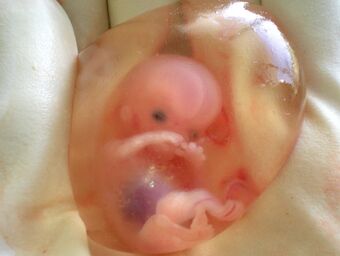

جنين بشري عمره 10 أسابيع محاط بالسائل السلوي في الكيس السلوي. | |

الصاء أو السائل السلوي Amniotic fluid هو السائل الذي يحيط بالجنين داخل الكيس السلوي أثناء الحمل. وحجم هذا السائل ليس ثابتا طوال فترة الحمل فهو يزيد من50 سم في الاسبوع الثاني عشر من الحمل إلي 400 سم في أواسط فترة الحمل إلي 1000 في الشهر الثامن من الحمل و يصل إلي 500 سم عند أواخر الحمل.

ينمو الكيس الأمنيوتي ويبدأ بالامتلاء، ولا سيما بالسائل بعد أسبوعين تقريبا من التلقيح. بعد 10 أسابيع في وقت لاحق يحتوي السائل على البروتينات والكربوهيدرات، والدهون، والدهون الفوسفاتية وسماد اليوريا والشوارد، والتي تساعد في نمو الجنين. ويستمر إنتاج السائل الذي يحيط بالجنين عن طريق السوائل التي تخرج من جلد الجنين حتى الأسبوع 14 من الحمل حتى النقطة التي يبدا فيها الجلد بالتقرن. خلال الأسابيع 8-11، يبدأ الجنين في ابتلاع والتبول فيه، وهذا هو السبب في السائل الأمنيوتي يحتوي على البول في مراحل لاحقة من الحملٍ. يزداد حجم السائل الأمنيوتي بنمو الجنين. تصل كمية السائل الأمنيوتي أعظم ما يكون عند الاسبوع 34 من عمر الحمل حيت تكون حوالي 800 مليلتر. ثم تنخفض كمية السائل إلى ما يقرب من 600 مليلتر في الأسبوع 40 من الحمل، والذي يكون عادة عند ولادة الطفل. يخرج السائل الأمنيوتي عندما تتمزق السلى. ومن المعروف أن هذا يحدث أثناء المخاض، كما هو معروف " تمزق الأغشية العفوي " (SROM). إذا تمزق قبل المخاض، يشار إليها بأنها "تمزق الأغشية قبل الأوان")غالبية السائل يبقى داخل الرحم حتى ولادة الطفل .ويمكن أيضا تمزيق الغشاء اصطناعيا، أي تمزيق الكيس الأمنيوتي، ويؤدي لخروج السائل إذا لم تتمزق السلى عفويا